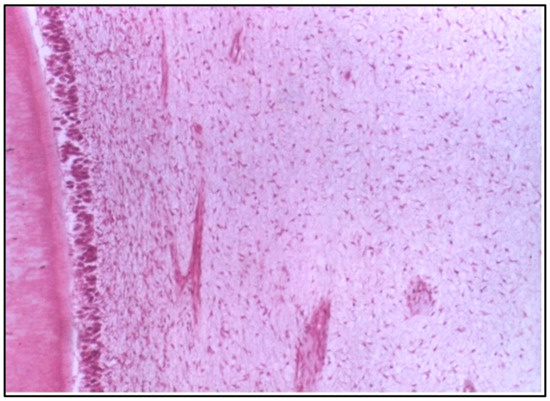

At 2 weeks, the specimens exhibited notable changes in the pulp tissue. The odontoblasts, which are the cells responsible for forming dentine, showed disorganization, indicating a disruption in their usual structure and function. There was also an increase in the vascular supply, suggesting an inflammatory response. The budding of new capillaries likely reflects the body’s attempt to repair or regenerate tissue. This reaction is typical of a mild to moderate inflammatory process following irritation or injury caused by the restorative material (Figure 1).

Regarding polyacid-modified composite resin, at 2 weeks, the specimens tested exhibited disorganization of odontoblasts and increased the vascular supply, indicated by the budding of new capillaries. This suggests an initial inflammatory response, possibly due to the material’s composition or the polymerization process. The increased vascularity can be interpreted as a reparative attempt by the pulp tissue to maintain homeostasis and facilitate healing [17].

Figure 1. Longitudinal section (LS) of the pulp (Group I, 2 weeks), showing disorganization of odontoblasts and an increase in the vascular supply to the pulp with the budding of new capillaries (H & E Stain, ×100).